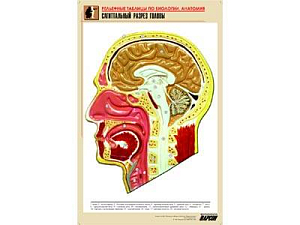

Объёмные модели и муляжи. Модель клетки, скелеты позвоночных, муляжи внутренних органов человека, барельефные таблицы по разделам зоологии и ботаники. На ЕГЭ и ОГЭ задания по анатомии и систематике — одни из самых частых. Объёмная модель отрабатывает пространственное представление так, как плоская картинка не может.